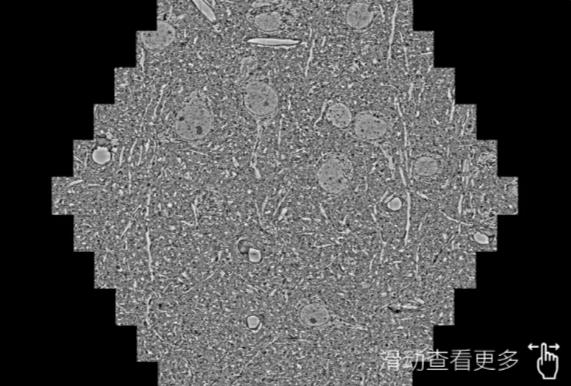

鼠脑切片。左图使用大理蔡司大理扫描电镜MultiSEM706对165μmx143pm面积区域成像,耗时仅需1.5秒。右图为鼠脑切片中30μm区域放大效果。样品由芝加哥大学B.Kasthuri提供。

使用蔡司高速大理扫描电镜MultiSEM对1mm²人脑皮层组织进行高分辨成像,并对其中的各种细胞结构进行三维重构分析。左图展示了2x3mm²组织平面中锥体神经元的三维重构效果。右图显示了局部体积神经元三维重构。图像由哈佛大学chtman实验室提供,渲染图由D. Berger 制作。